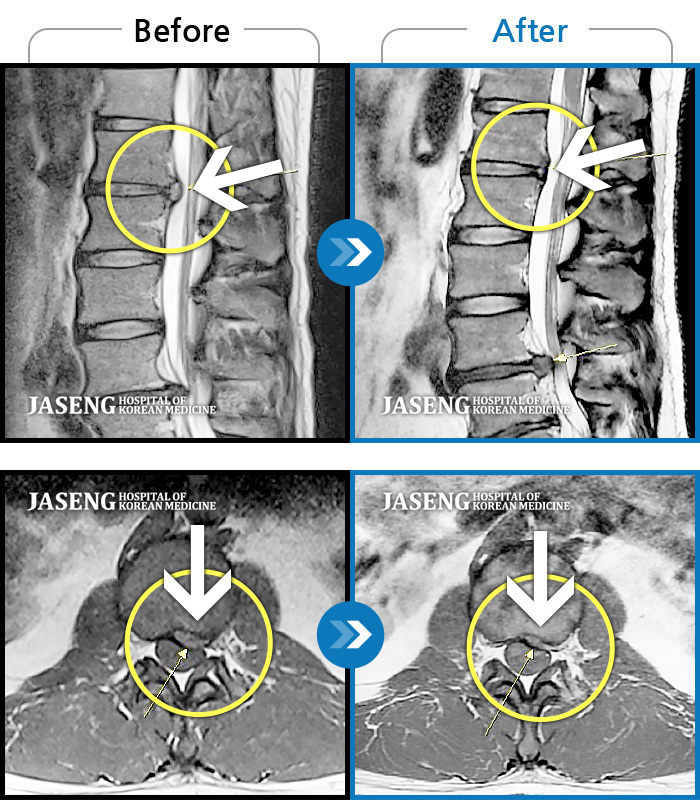

Before

After

환자에게 사전 동의를 받아 동일 조건에서 촬영되었습니다.

개인에 따라 치료 후 부작용이 발생할 수 있으니 의료진과 상담 후 치료를 진행하시기 바랍니다.

왼쪽 종아리가 많이 당기고 걸을 때 절뚝거림이 심했습니다.

양측 허리부터 양측 골반 통증, 좌측 허벅지부터 종아리 후면부 통증 및 저린감